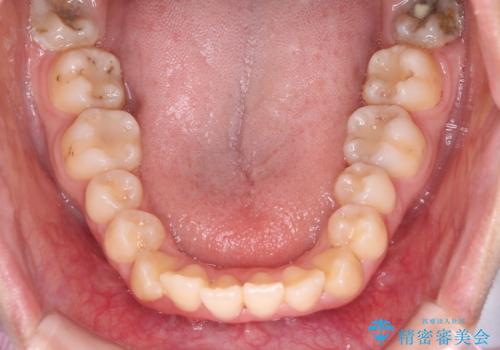

【ハーフリンガル】口元を下げたい!

- 口元が出ていることを主訴に来院されました。

歯を抜いてスペースを作ることで、前歯を下げることができました。

ハーフリンガルということで治療期間が3年近くかかりましたが、口元もしっかり下がり満足していただきました。